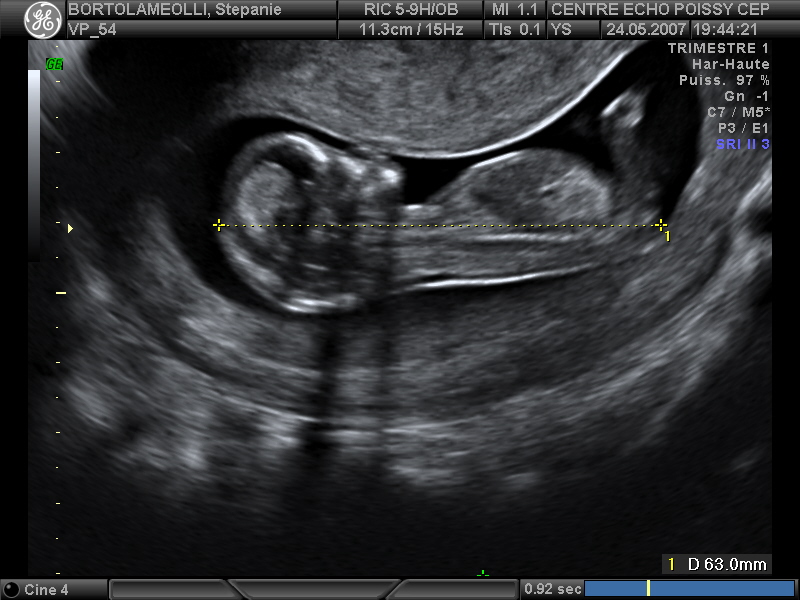

Echographies

Mai 2007